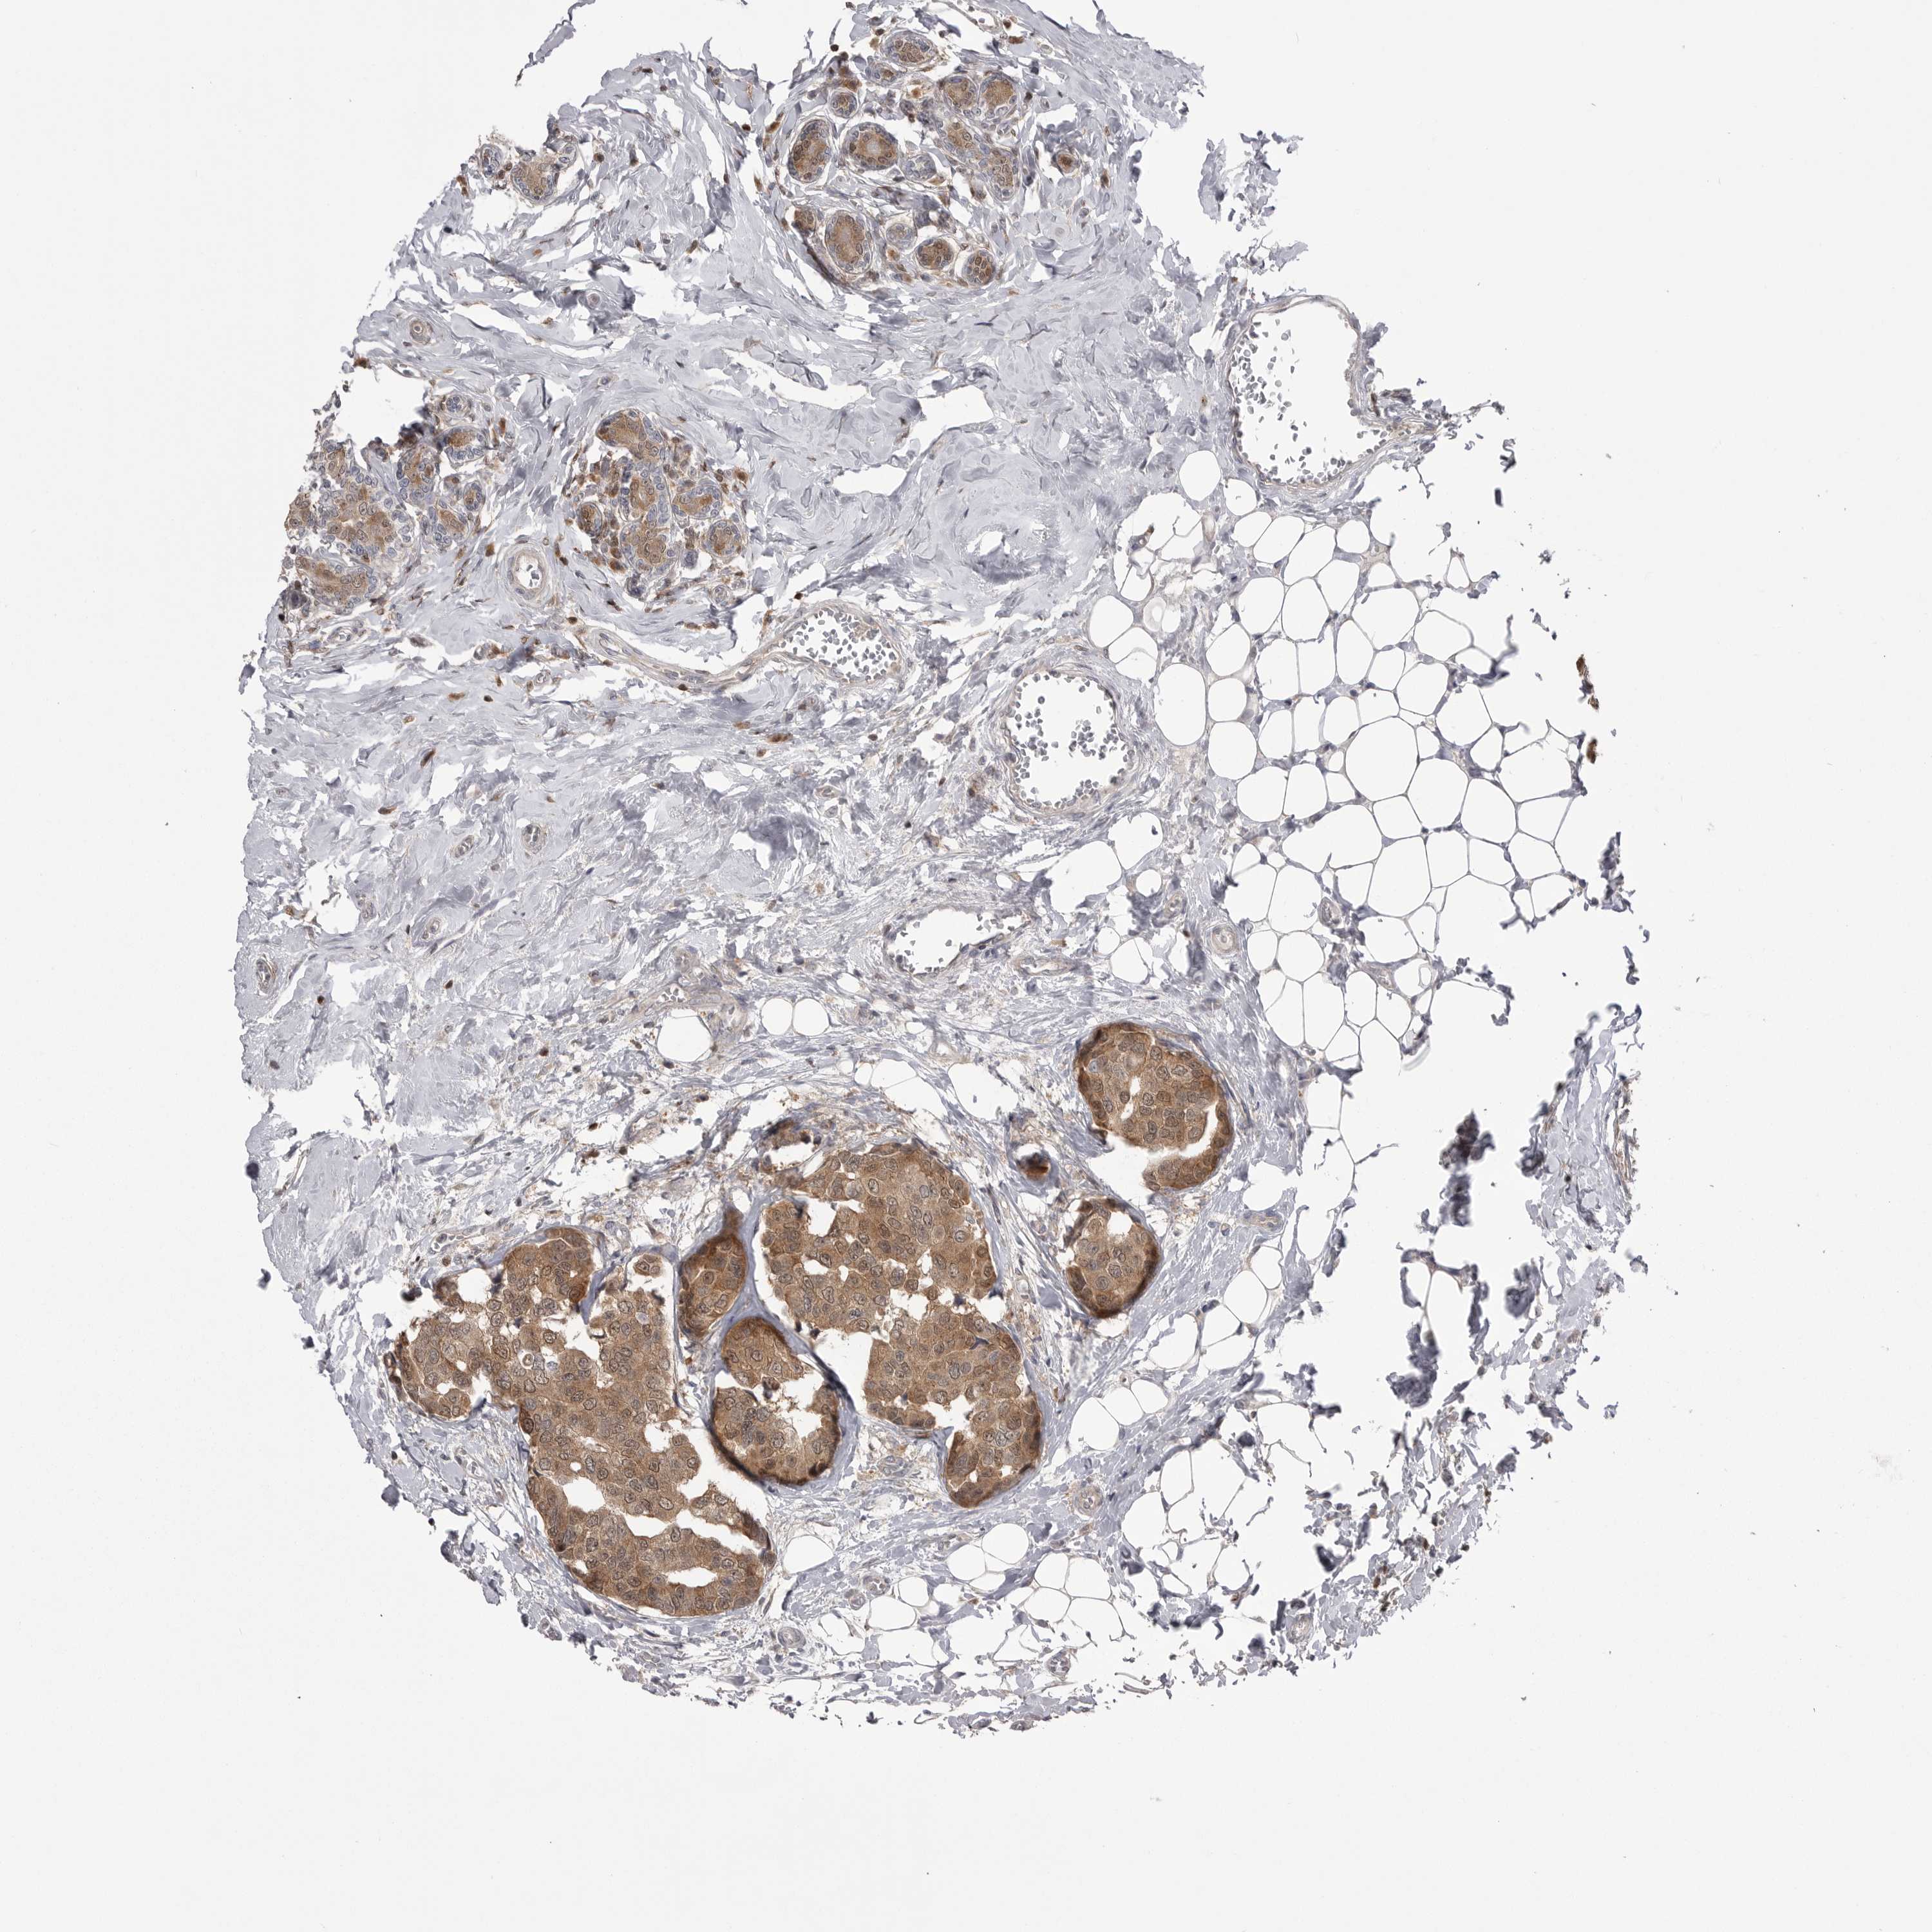

BRCA TCGA BRCA VALIDATION PROTEIN EXPRESSION

ANTIBODIES

AND

VALIDATION